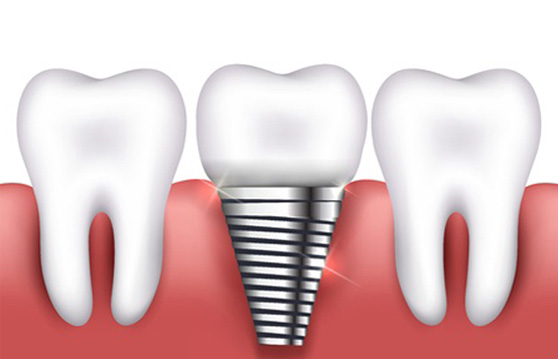

Ä¡¾Æ°¡ ±úÁö°Å³ª, ½Å°æÄ¡·á ÈÄ ÀÚ¿¬Ä¡ º¸È£¸¦ À§ÇØ ¾º¿ï ¶§, Ä¡¾Æ°¡ ºüÁ³À» ¶§ À̸¦ ´ëüÇϱâ À§ÇØ º¸Ã¶Ä¡·á°¡ ÇÊ¿äÇÕ´Ï´Ù.